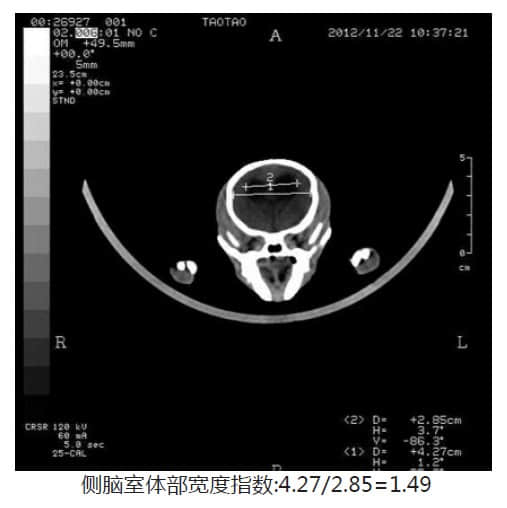

C T 影 像所见: 双侧大脑半球对称,灰白质对比正常,未见局灶性密度异常,中线结构居中,双侧侧脑室、第三脑室及四脑室对称性中度扩大,侧脑室宽1.33cm, 侧脑室的上角和下角通路异常增宽,幕下小脑、脑干无异常。囟门未闭合,宽1.36cm。侧脑室体部宽度指数:4.11/2.66=1.5。

脑积水的诊断标准

在宠物诊疗上没有一个准确的标准来判断脑积水,但通过许多病例的积累于鉴别,得出一个规律,利用侧脑室体部宽度指数来判断脑水肿。但有时候也可以依靠大量脑水肿病例的经验来判: